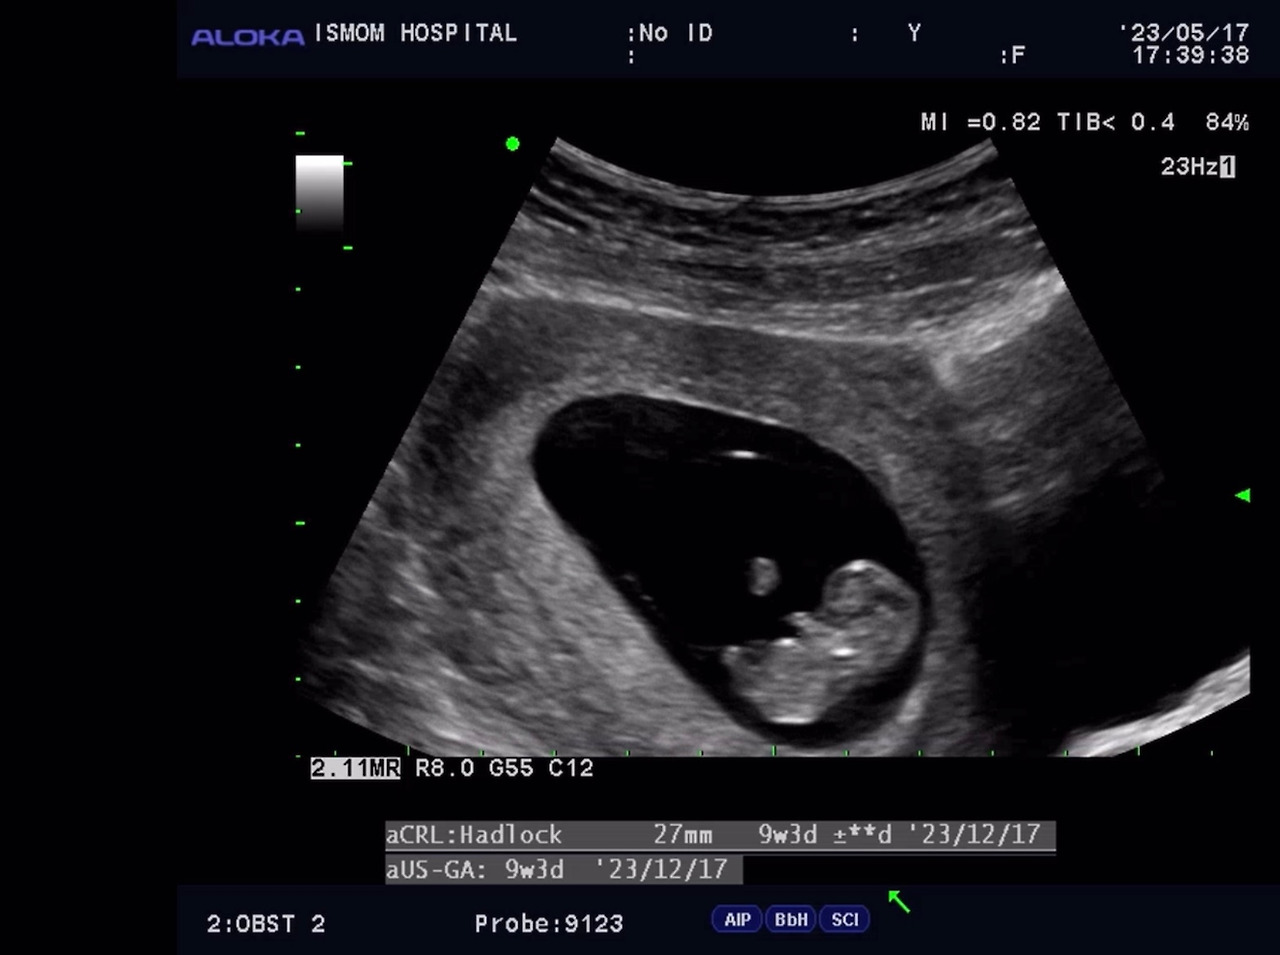

그러다 갑작스레, 소중한 아이가 찾아왔다.

그리고는 나는 또 다른 형태의 사랑을 하고 있다. 원래는 나를 꼭 안던 남편이 이제는 내 배도 함께 쓰다듬는다.

내 아기는 초음파로도 귀엽다